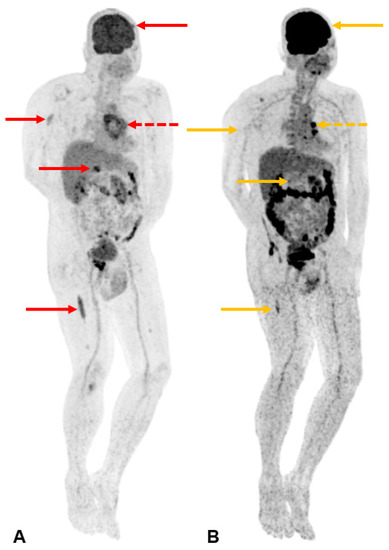

A subsequent 18-fluorodeoxyglucose (FDG) whole-body positron emission tomography-computed tomography (PET-CT) study (A) shows intense FDG avidity at multiple sites, including the index sternal lesion (SUVmax 4.9) [indicated by the dotted red arrow] and other foci in the left frontal skull (1.5 cm, SUVmax 4.6), right humerus (4.4 cm, SUVmax 3.5), lower thoracic vertebra (2.1 cm, SUVmax 7.4), and right femur (9.5 cm, SUVmax 4.7) [indicated by solid red arrows in a cephalocaudal direction, respectively]. The patient’s multifocal osteolytic lesions, anaemia with a haemoglobin level less than 10 g/dL, and a bone marrow clonal plasma cell percentage of 60% were consistent with a diagnosis of multiple myeloma, as set out in the 2014 International Myeloma Working Group (IMWG) criterion [8]. Bone disease is present in up to 90% of multiple myeloma patients. It is related to increased osteoclastic activity, mediated by osteoclast-activating factors and local cytokines such as interleukin-6 and tumour necrosis factor-α. This can result in diffuse osteoporosis, solitary or multiple osteolytic lesions, fractures, and hypercalcemia from increased bone turnover. Imaging plays a pivotal role in the detection and assessment of the extent of bone disease. In suspected multiple myeloma, low-dose whole-body CT or FDG PET-CT is recommended to identify osteolytic lesions (>5 mm in size) [9]. Focal osseous radiotracer uptake on FDG PET-CT alone is insufficient to fulfil the IMWG criterion for bone lesions in the absence of osteolysis. If CT or PET-CT is negative or inconclusive, MRI can be a more sensitive modality in detecting focal lesions (>5 mm in size) before osteolytic bone destruction is evident [9]. Radiographic skeletal surveys are no longer recommended as a first-line investigation. In terms of staging and prognostication, the 2005 International Staging System (ISS) score considers two parameters—high serum β2-microglobulin levels reflect a high tumour burden, while low serum albumin levels are related to the presence of inflammatory cytokines such as interleukin-6 in the myeloma microenvironment. The Revised International Staging System (R-ISS) [10] incorporates two additional parameters that demonstrate impact on survival—the elevation of serum LDH level reflects a high proliferation rate, while the presence of high-risk cytogenetic abnormalities (namely, del(17p), translocation t(4;14)(p16;q32), or translocation t(14;16)(q32;q23)) are associated with aggressive biological behaviour. Patients with R-ISS stage I, II, and III have 5-year overall survival rates of 82%, 62%, and 40%, respectively [11]. Prompt treatment of active multiple myeloma is essential to prevent further complications and organ damage. The addition of autologous stem cell transplantation has been associated with longer progression-free survival [12], while novel agents such as daratumumab have also increased treatment efficacy [13]. Our patient was able to achieve response with a regimen of daratumumab, bortezomib, thalidomide, and dexamethasone (D-VTd). The precordial lump was no longer palpable after the first cycle of systemic therapy in the repeat FDG PET-CT study conducted three months after the initiation of treatment, showing a marked improvement in the previously seen lesions (B). Local radiotherapy to the index sternal lesion was not offered to the patient due to the prompt response to systemic therapy with resolution of the pain associated with the precordial lump. The other osseous lesions were also not symptomatic, negating the need for palliative radiotherapy [14]. Six months after the initial diagnosis, our patient also underwent autologous stem cell transplant which was shown to improve progression-free survival in the CASSIOPEIA trial [15].